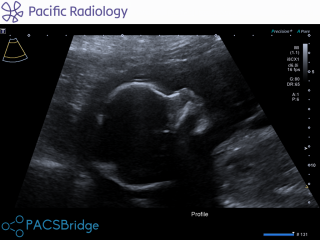

Hi i am 37 and pregnant with my second child. Had my bloods done at 20 weeks and anatomy scan also done scan was good but then today got call from midwife saying she got blood results and they have come bk high risk of down syndrome 1 in 140 chance. I now waiting hear from hospital what happens next for testing etc. I feel now distant to my pregnancy and now just super scared. Can any mums please help with advice as i so worried and a mess. Will this mean my child will have it etc. Attached is scan pic of our little girl. I am in nz